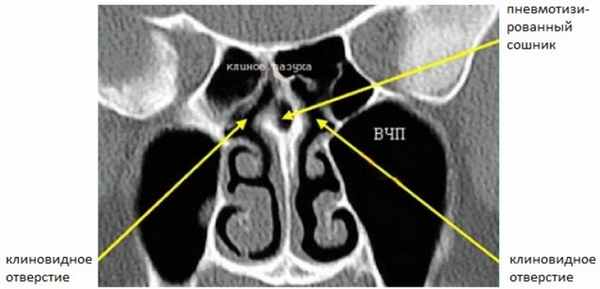

Задний ОМК (Рис. 3) расположен в сфеноэтмоидальном кармане, дренирует задние решетчатые ячейки и клиновидные пазухи.

Рисунок 3. КТ полости носа. Сошник разделяет два отверстия клиновидных пазух, которые расположены в сфеноэтмоидальном кармане. Сошник пневматизирован (норма).

Сошник разделяет два отверстия клиновидных пазух. При хроническом синусите этот комплекс вовлекается реже, потому что в нем более редко встречаются анатомические варианты. Сагиттальная реконструкция ОМК, демонстрирующая искривленный край полулунного хода с нижней складкой слизистой, покрывающей крючковидный отросток показана на рисунке 4. Также здесь виден лобный карман.